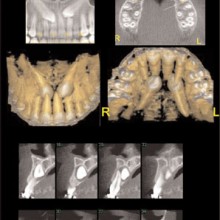

MAXIMUM INTENSITY PROJECTION (MIP) can be used to highlight features. The anatomic features associated with the brightest pixel or voxel intensity are projected on the display screen. This method creates a high-contrast image, but the brighter pixels/voxels may mask or superimpose over less-bright pixels, thus potentially hiding important anatomic features. MIP projections of a CBCT volume or slab (right or left sides) may be a useful method to produce constructed panoramic and cephalometric images for orthodontic purposes (Figure 3). Shaded surface Rendering (SSR) is useful for high-contrast imaging such as bone. SSR techniques allow the operator to set a pixel or voxel intensity threshold that excludes structures lower than the selected threshold, and renders all structures greater than the selected threshold (Figure 3). SSR creates a three-dimensional model that can be rotated as an object to be viewed from any angle. When the tissue contrast is not high, then the selected threshold may not perfectly render the desired anatomy. Volume rendering (VR) also creates a three-dimensional model using no

pixel/voxel threshold for data exclusion (Figure 4). The entire volume is always loaded but tissues are interactively grouped by voxel intensity, and each group can be assigned with a color and transparency value prior to projecting the volume onto the viewing monitor. The operator can rotate the VR model and change the opacity levels, thus providing the sense of peeling away tissues layer by layer. VR is a good way to visually understand the anatomic relationships between structures, and can be used effectively for treatment planning and as a communication tool.

IMPLANTS: Implants that are used to replace missing teeth, for anchorage to mobilize teeth, or dental segments and, in some cases, can be restored to optimize function and esthetics. Implants need to be located where they will have the best chance for success. Prosthetic, anatomic, and biomechanical requirements independently or in combinations are key considerations to be resolved. Three-dimensional imaging techniques can play a significant role revealing the anatomic considerations and linking them to the prosthetic and biomechanical treatment options (Figures 5, 6).